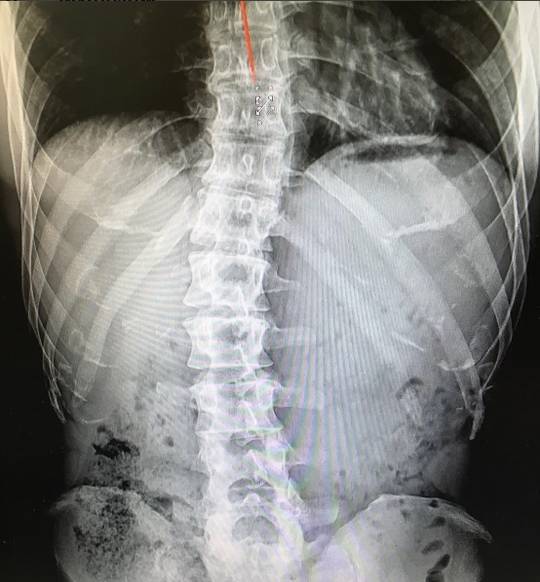

김종국이 등 근육사진 공개 후 일부 네티즌의 설왕설래가 이어지자 척추측만증 엑스레이 사진을 공개했다. 김종국은 11월 4일 자신의 인스타그램에 "고등학교때 처음 허리 통증으로 쓰러졌을 때부터 쭉 가지고 있던 척추측만증. '이런 허리로 어떻게 그런 몸을 만들죠'한다. 난 만들었다. 아니 만들고 있다. 이 휘어진 척추, 무언가로는 잡아줘야 하니까"라는 글을 남겼다.

김종국은 11월 4일 자신의 인스타그램에 "고등학교때 처음 허리 통증으로 쓰러졌을 때부터 쭉 가지고 있던 척추측만증. '이런 허리로 어떻게 그런 몸을 만들죠'한다. 난 만들었다. 아니 만들고 있다. 이 휘어진 척추, 무언가로는 잡아줘야 하니까"라는 글을 남겼다.

이어 김종국은 "나약한 인간들이 불가능이라고 입으로만 떠들고 온갖 핑계 삼아 술 먹고 놀러 다니고 따뜻한 이불 속에서 편하게 쉴때, 난 이 악물고 잠 줄이고 이러고 산다. '저게 말이 돼? 분명 이럴 거야' 이것 좀 하지 말고 살자. 자신이 못한다고 단정짓고 해낸 사람을 오히려 폄하해야 위로가 된다는 거 알고는 있는데, 이제라도 본인이 진짜 못할 거라고 믿고 산 거 지금 하나라도 시작해보자"라는 글을 덧붙였다.

더불어 김종국은 "남들이 안 된다고 믿는 거 해내는 즐거움. 좀 하나라도 느껴보자. 딱해서 그래. 누가 내 등 사진 보고 척추가 참 곧다고 해서, 딱해서"라고 덧붙였다.